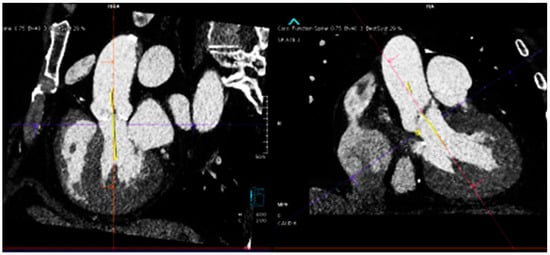

| Santaló-Corcoy [20] | 200 CTs (35 for training, and 17 for testing) | Manual CT measurement by an expert cardiologist using 3Mensio. | Correlation between manual and automated measurements | DL algorithms (MeshDeformNet) for landmark detection followed by segmentation | mean absolute relative error was within 5% for most measurements, except for coronary height (11.6% and 16.5%). |

| Theriault-Lauzier [21] | 94 CTs of severe AS (K-fold cross-validation with K=) | Manually segmented AV annulus | Correlation between manual and automated measurements | recursive multiresolution CNN for localization of the AV annulus centroid | average out-of-plane localization error of 0.9 ± 0.8 mm for the evaluation dataset. The proposed algorithm is on par with automated methods for localization and approaches in providing an expert-level accuracy. |

| Samin [22] | 60 CTs (24 retrospectively, 36 prospectively) | fluoroscopy | accurate prediction (<5° difference) of LP | Not detailed | Automated 3D analysis of CTs accurately predicted the LP aortic annulus and the corresponding C-arm position required in 8/8, 16/17, and 10/11 in patients with mild, moderate, or severe calcifications. |

- Santaló-Corcoy, M.; Corbin, D.; Tastet, O.; Lesage, F.; Modine, T.; Asgar, A.; Ben Ali, W. TAVI-PREP: A Deep Learning-Based Tool for Automated Measurements Extraction in TAVI Planning. Diagnostics 2023, 13, 3181. [Google Scholar] [CrossRef]

- Samin, M.; Juthier, F.; Van Belle, C.; Agostoni, P.; Kluin, J.; Stella, P.R.; Ramjankhan, F.; Budde, R.P.; Sieswerda, G.; Algeri, E.; et al. Automated 3D analysis of multislice computed tomography to define the line of perpendicularity of the aortic annulus and of the implanted valve: Benefit on planning transcatheter aortic valve replacement. Catheter. Cardiovasc. Interv. 2014, 83, E119–E127. [Google Scholar] [CrossRef]